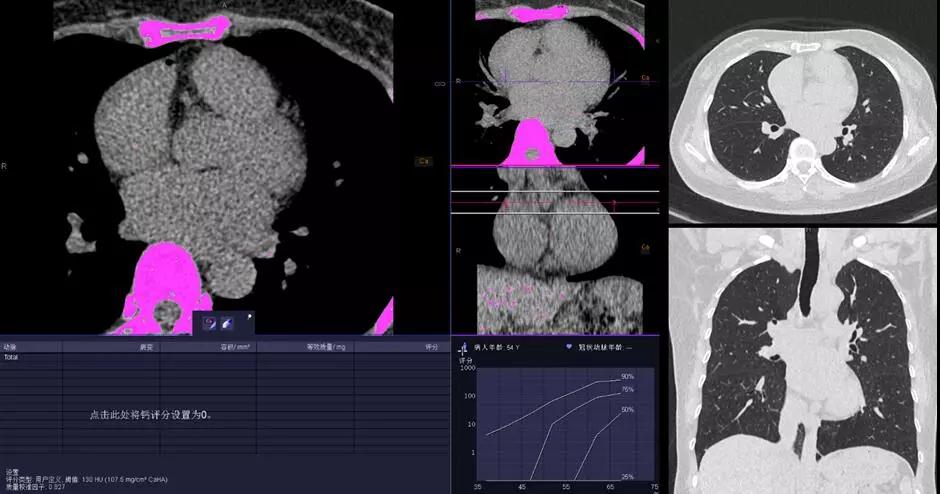

2.冠心病和腫瘤早期檢測,胸片劑量的CT掃描,徹底實現心肺疾病CT篩檢的常規臨床化。只需要一次胸片檢查的輻射劑量,即可完成高分辨率的肺部成像和冠脈成像;在極低的輻射劑量下同時可以保持優秀的對比信噪比(CNR),與傳統 CT 相比輻射劑量減少達90%。配合Stellar Infinity 全息光子探測器優異的低對比探測能力,使 SOMATOM Force成為隱匿性病變早期檢測的理想設備。為無癥狀高危患者的檢查設定了一個新的檢查標準。這無疑將改寫CT掃描的歷史。

△KV純譜技術高端體檢一站式體檢——鈣化積分+肺一站式檢查